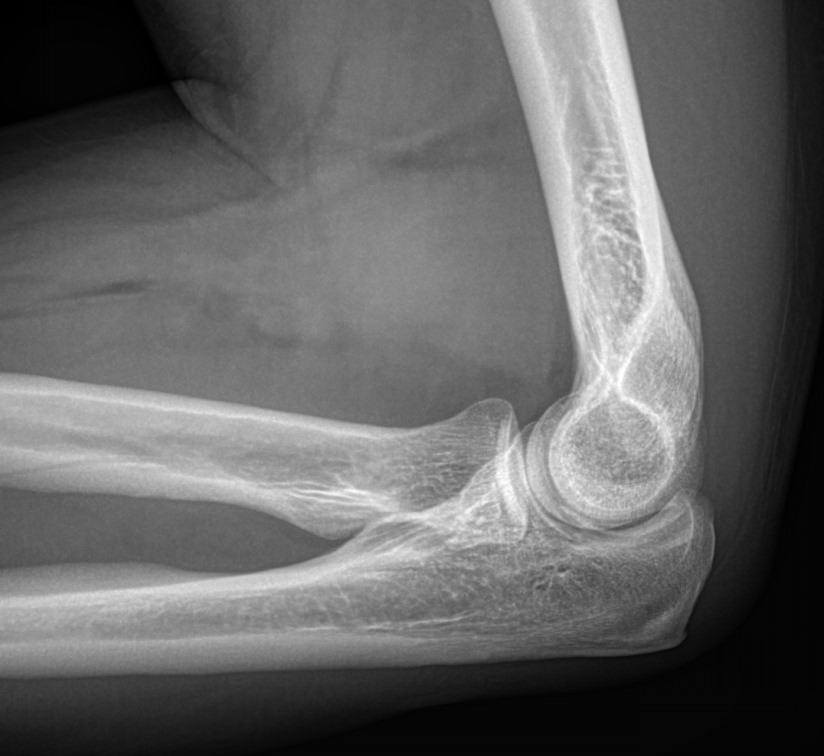

Локтевой сустав считается сложным, он состоит из 3 костей, плечевой, локтевой и лучевой, образующих, соответственно, 3 сустава. Такое строение позволяет свободно двигать рукой и поворачивать ее, обеспечивая достаточный для человека объем движений. Патологии сустава серьезно ухудшают двигательную активность и вызывают болезненные ощущения.

При обращении с типичными жалобами на локтевой сустав врач ― ортопед, травматолог или онколог ― назначает рентгенографию в качестве первичной диагностики. Обычно, этого бывает достаточно для постановки диагноза и выбора метода лечения. В более сложных или запущенных случаях всегда можно дополнить исследование МРТ, КТ или УЗИ.

Что покажет рентген локтевого сустава

• Отек мягких тканей;

• Конгруэнтность и состояние суставных поверхностей, например, наличие эрозии и уплотнение суставных поверхностей, а также костные разрастания

• Состояние суставной щели ― сужение, выпот, обызвествление капсулы;

• Структура костной ткани ― типичная, деструкция или участки повышенной плотности и вздутия, остеопения, иные патологии;

• Травмы ― переломы;